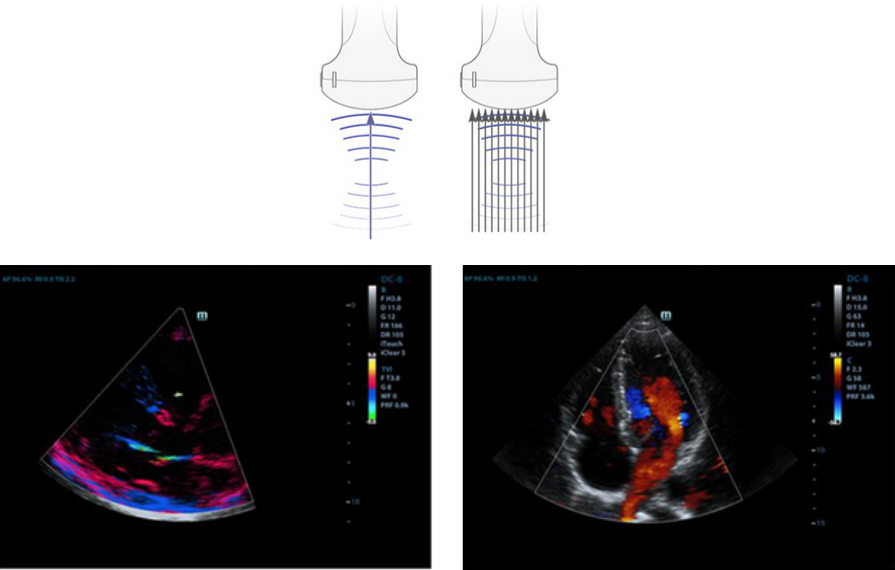

Formazione raggi multipli

Tasking di massimo 12 volte per un raggio trasmesso, con eccellente risoluzione temporale e frequenza di fotogrammi pi├╣ alta.